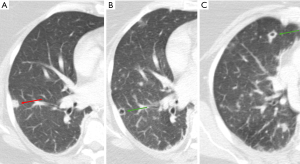

Mycobacterium TB infection

Cavitation is a hallmark of post-primary TB, occurring in approximately 50% of patients (7). The likelihood of cavitation correlates with higher sputum mycobacterial loads (8). Moreover, cavitation is an uncommon feature of primary TB, which is characterized by inflammation and granuloma formation that does not usually lead to the tissue destruction that causes cavitation (8,17). Cavitation primarily occurs in post-primary TB, when the bacteria reactivate from dormant state and the immune system’s response leads to more extensive tissue damage and cavitation (8,17). Hence, radiologically, primary TB is more likely to show intra-thoracic lymph node enlargement, pleural effusion and lower lobe lung lesions. Cavitation is less characteristic of these initial presentations, seen only in 10–30% of cases (17). Typical imaging findings of post-primary TB include a predilection for the upper lobes, particularly the apical and posterior segments (7). Patchy and poorly defined consolidations are often the earliest findings (7,8). Cavities often form within areas of consolidation, exhibiting variable wall thickness, ranging from thin and smooth to thick and nodular walls (Figures 7-9) (8). Air-fluid levels are seen in 10–20% of tuberculous cavities (18). Endobronchial dissemination can lead to tree-in-bud opacities, and pleural effusion is common (8).